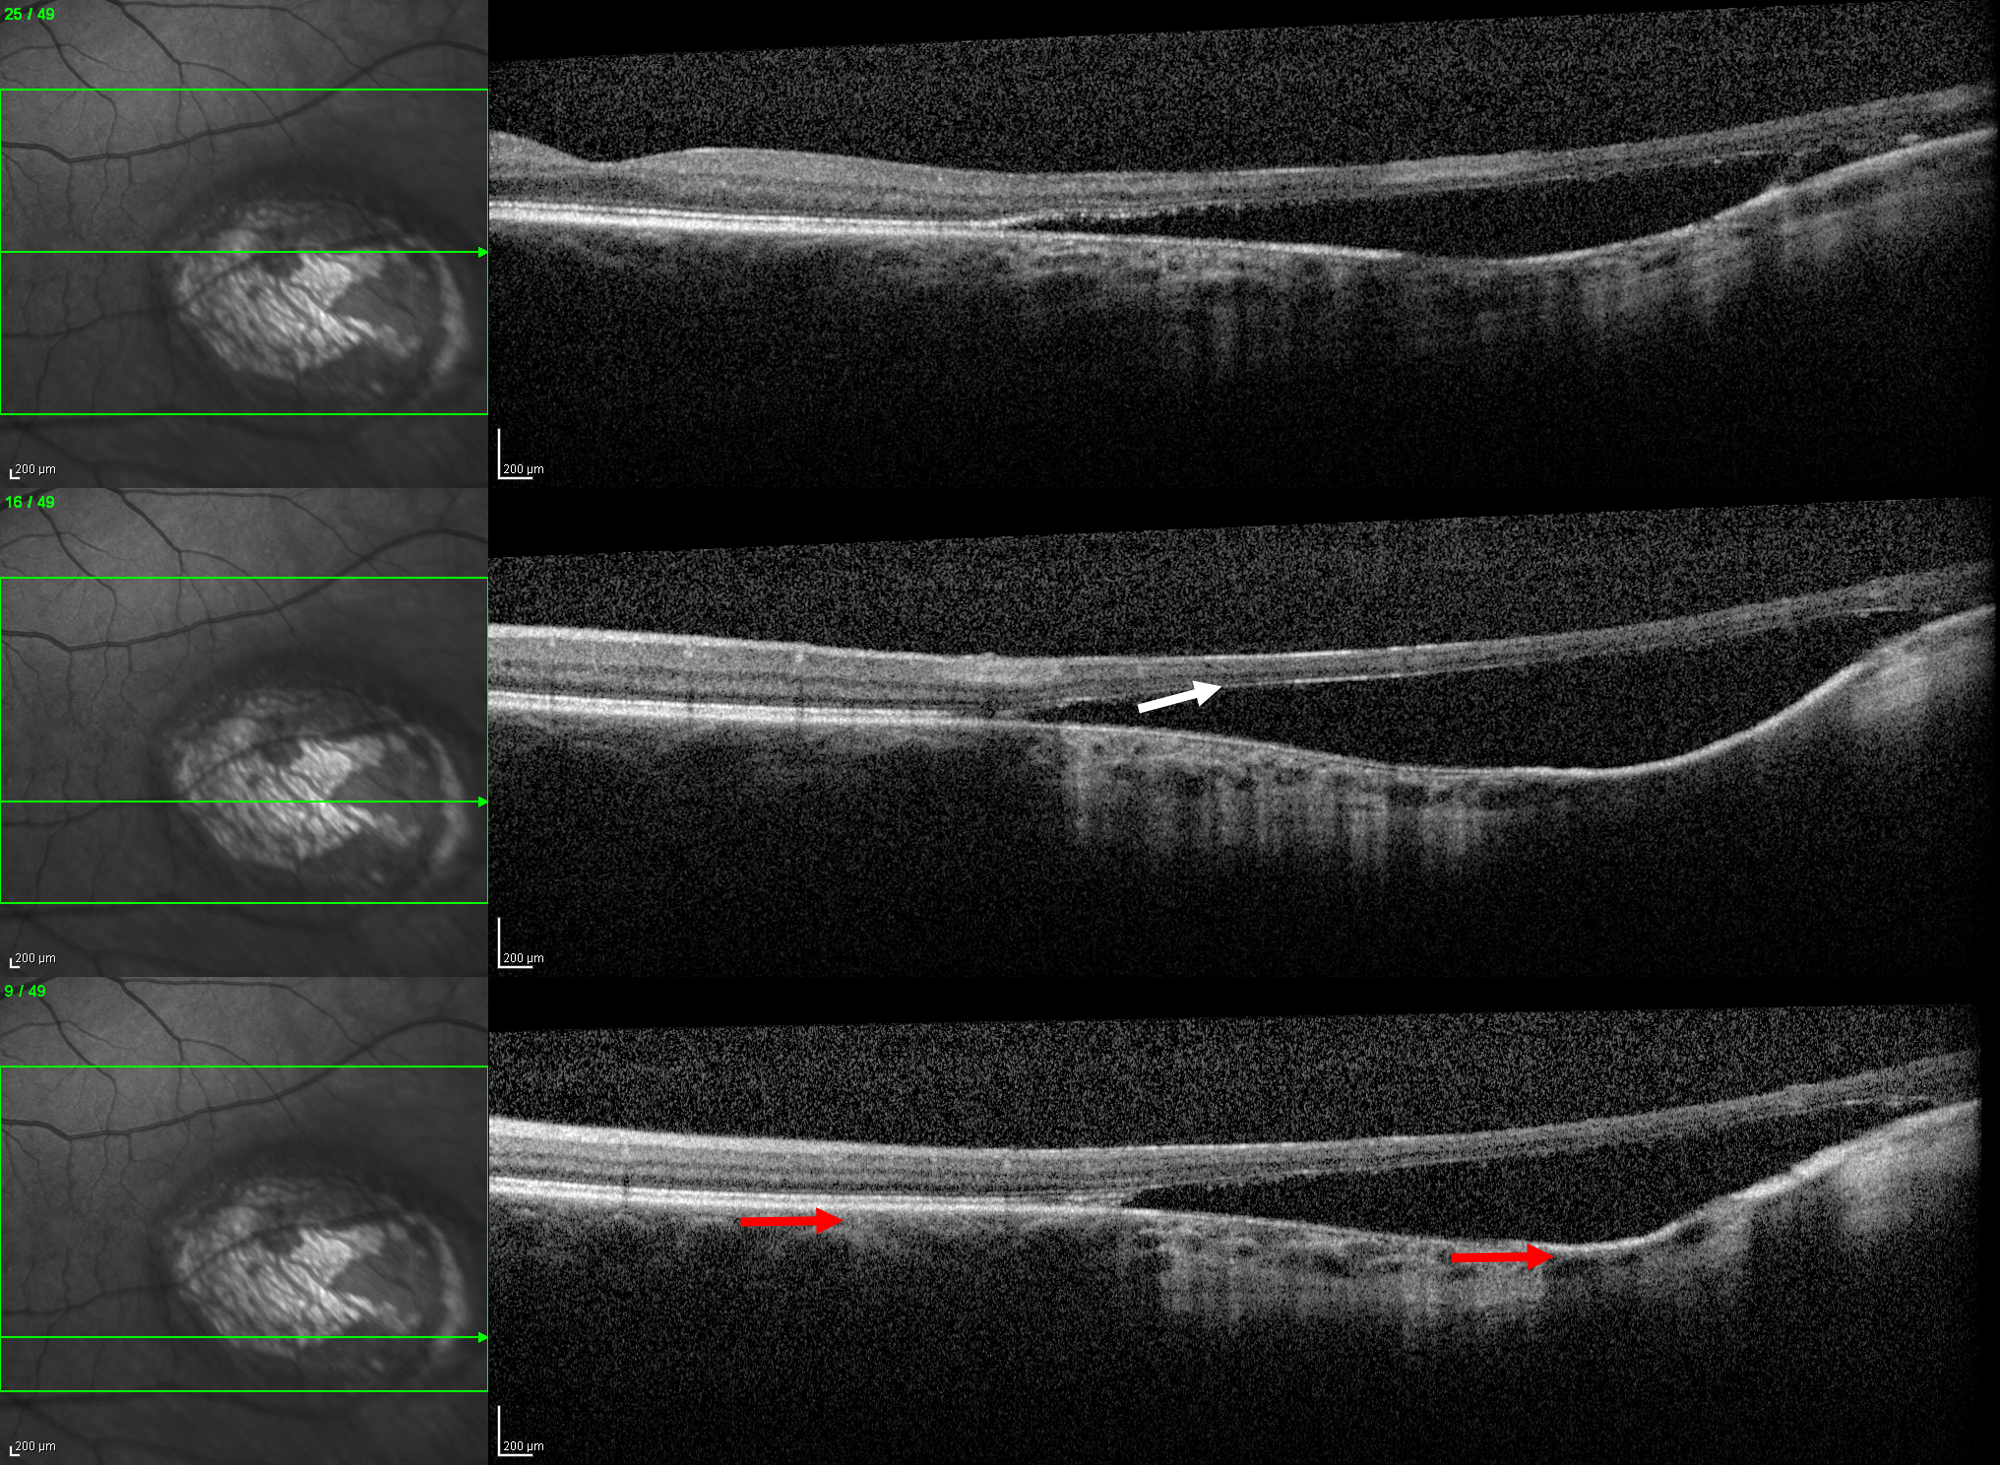

Ocular toxoplasmosis is an infection in the eye caused by the parasite Toxoplasma Gondii. A common retinal finding in its inactive stages are pigmented retinochoroidal scarring. The retinal function in the affected area assumingly reflects the amount of retinal involvement. This case report presents a 48-year-old woman who has a long-standing large retinochoroidal scar in the temporal posterior pole of her left eye. She had not experienced any visual symptoms, and no recurrent infections had occurred as far as she knew. She has a scotoma in her nasal visual field that her optometrist detected by a coincidence when she was in her twenties. The corresponding visual field defect is smaller and less deep than what may be expected from the structural appearance of the scar. The reported case demonstrates, that the visual function may be well preserved in the visual field corresponding to a retinochoroidal scarred area due to toxoplasmosis, in spite of loss of structures in the outer retinal layers as seen with OCT.